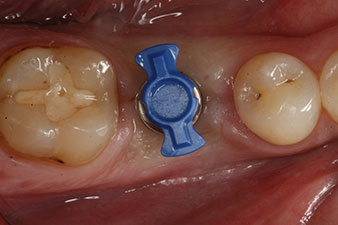

Après cicatrisation des tissus mous, la stabilité de l’implant a été mesurée une nouvelle fois avant la pose de la restauration prothétique.

Les deux valeurs étaient pratiquement inchangées, situées entre la plage moyenne et la plage haute - la valeur la plus basse étant toujours utilisée comme valeur de référence qui détermine le traitement.

Par conséquent, il a été possible d’enregistrer une ostéo-intégration réussie et une stabilité biologique correcte, permettant également de prendre une empreinte durant la même séance.